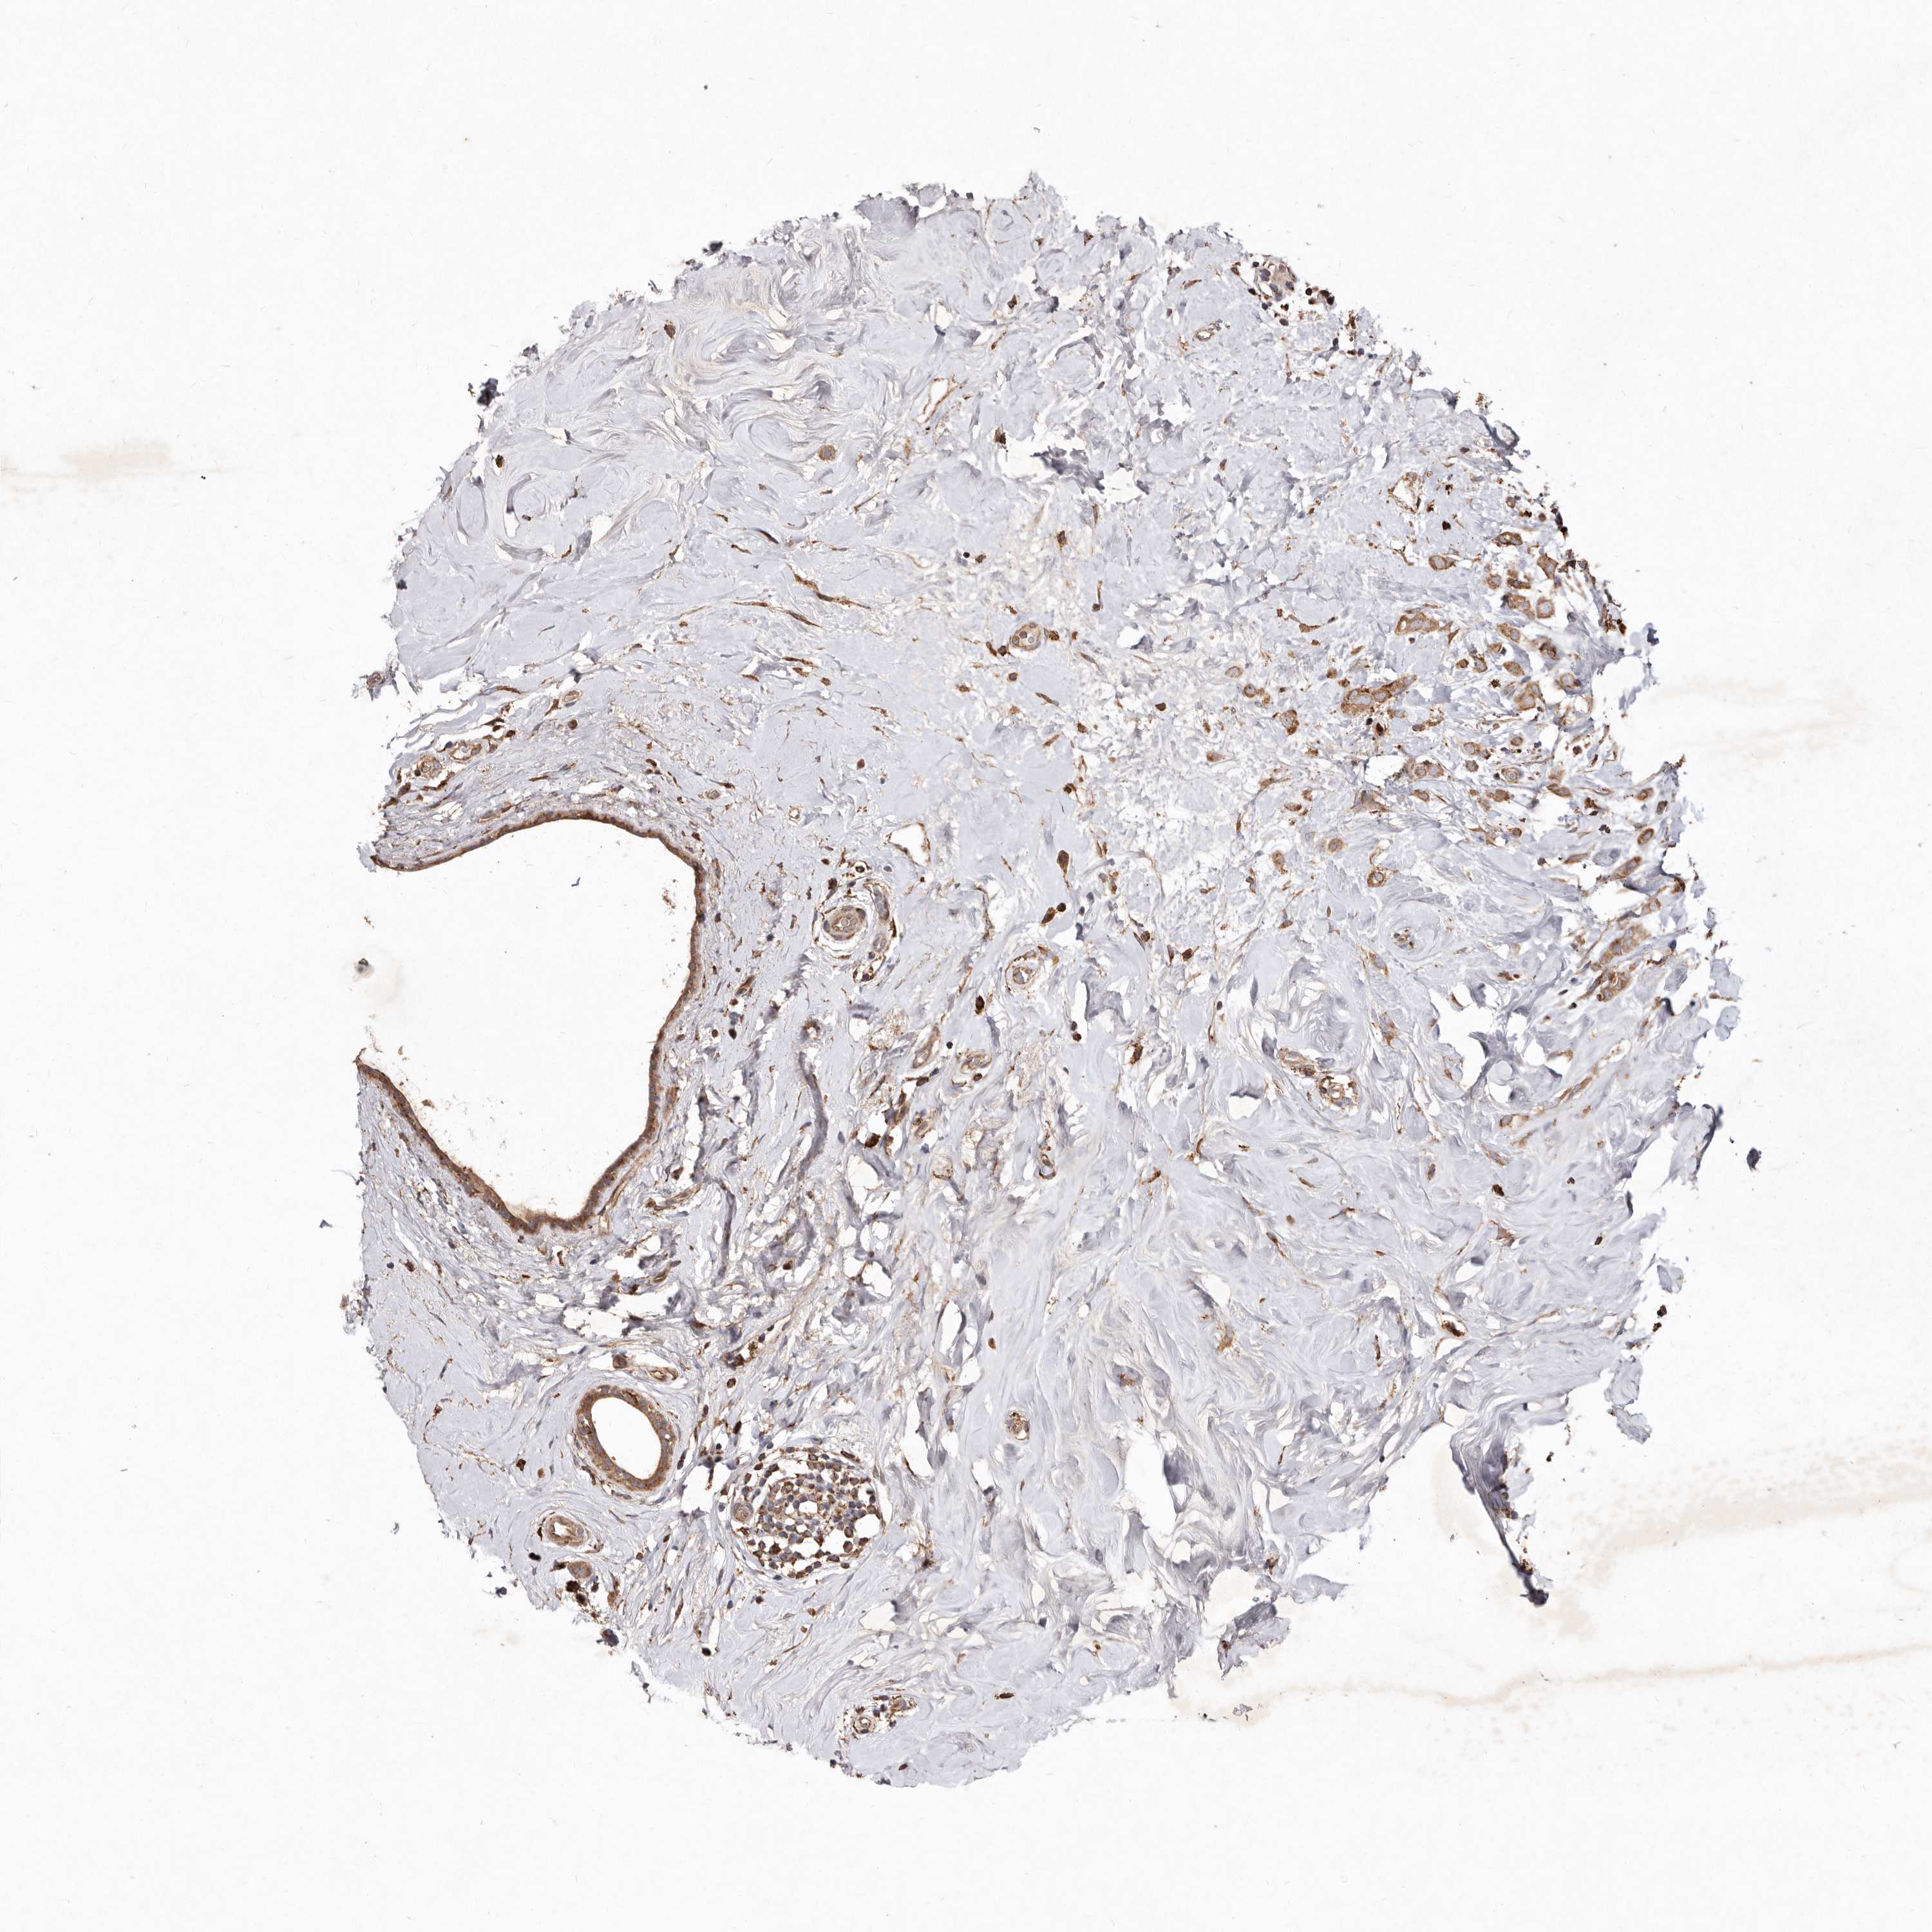

CANCER BREAST CANCER Show tissue menu

BRCA TCGA BRCA VALIDATION PROTEIN EXPRESSION

ANTIBODIES

AND

VALIDATION